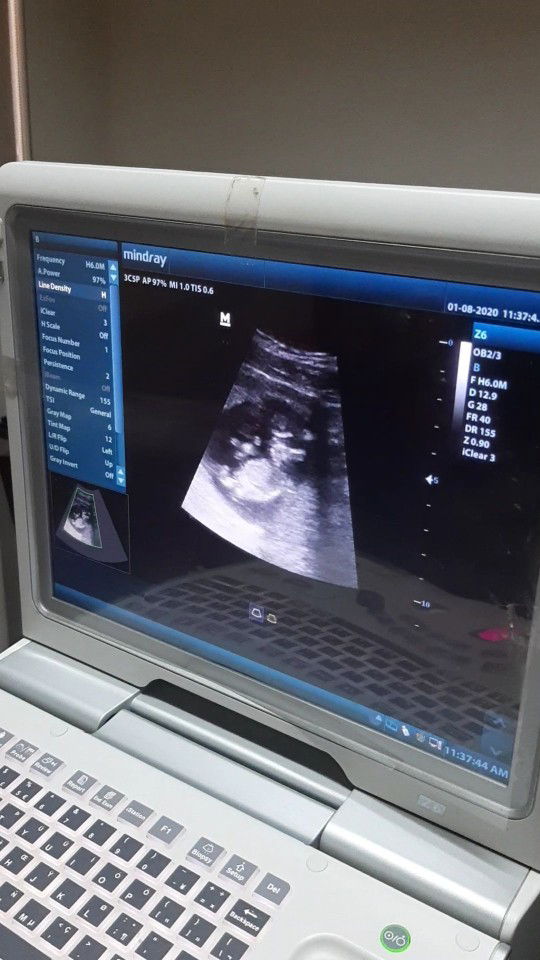

my baby at almost 12 weeks ❤

malikot na si baby hahaha